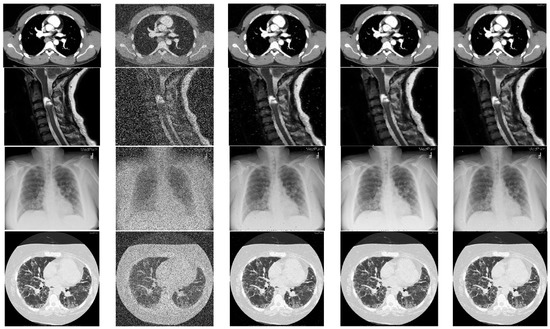

A subjective comparison is performed on a small sample of standard images as shown in Figure 6 as well as randomly selected medical images of MedPix dataset and the restoration results are shown in Figure 8, Figure 9 and Figure 10. In Figure 8, the restored images of NWM [29], SRM [40] and AEPWM [41] have some traces of noise clearly visible on the restored images whereas AFIDM [42], QSAF, TSA and the proposed filter de-noised the noisy image well. It is clear from the visual results that the proposed filter has preserved the edges and detailed regions of the Lena image very well as compared TSA, QSAF and other competing filters. The performance of the proposed filter is tested on detailed images, i.e., Baboon and Barbara, of size 512 × 512 at high noise densities, 50% and 60% RVIN, and the results are tabulated in Figure 9. It can be seen from the restored results that the proposed filter has effectively preserved the edges and fine details in both the images. Similarly, when the proposed technique is further tested on medical images of MedPix dataset as shown in Figure 10, it is clear from subjective results that the proposed filter outperforms QSAF and AFIDM filters. Figure 11 shows EPI values of different de-noising methods for Lena image at 30% noise ratio. It is evident from quantitative as well as subjective comparisons that the proposed filter gives best results and outperforms many existing filters against different noise densities ranging from low to high.

Figure 10.

Shows image restoration results on medical image dataset. 1st column are the original images from MedPix database, 2nd column are the noisy images with 40% RVIN, third column shows de-noised results using AFIDM filter, fourth column shows de-noised results using QSAF and fifth column shows restoration results of proposed filter.